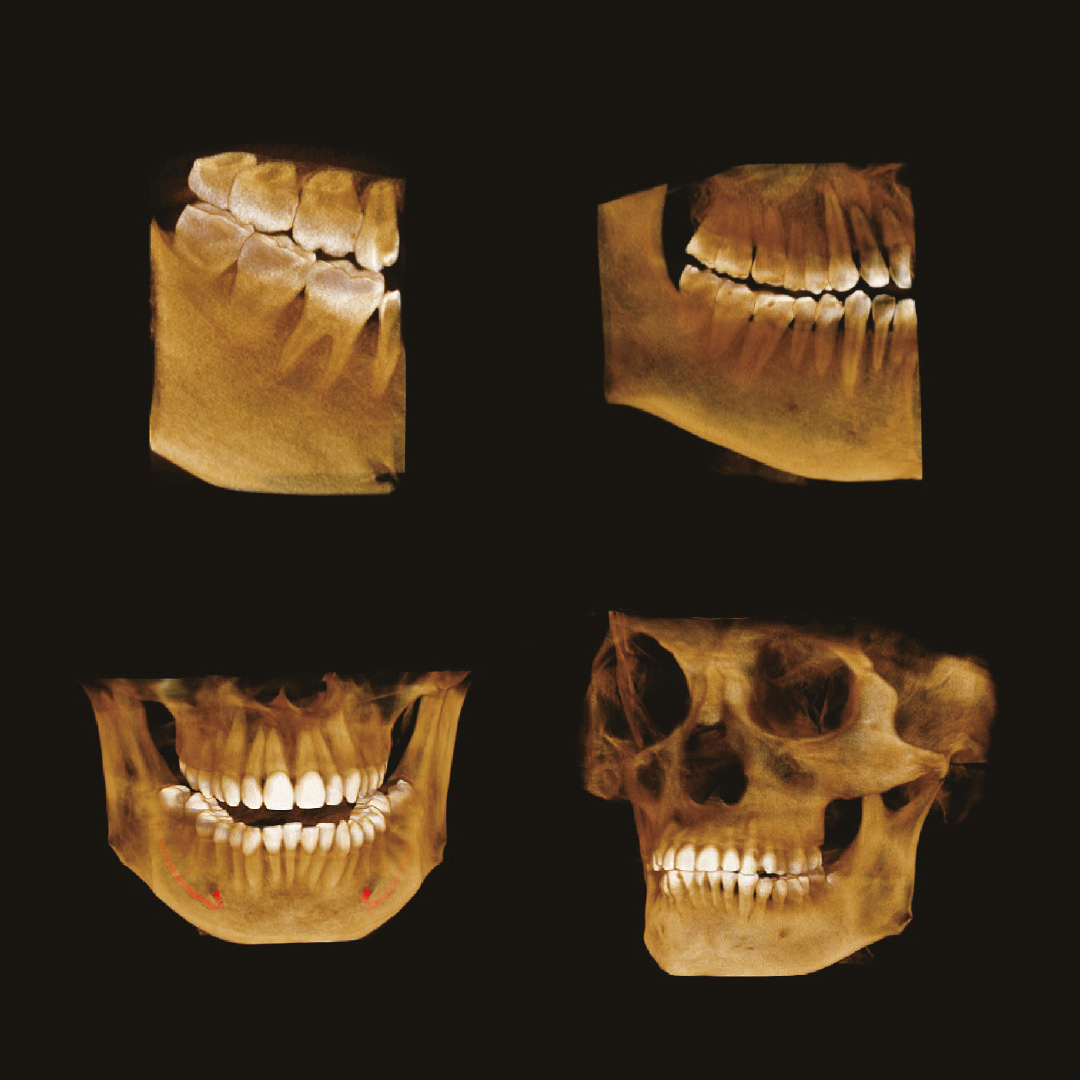

Пример 3D исследования дентального компьютерного 3D томографа Volux 55 Genoray.jpg